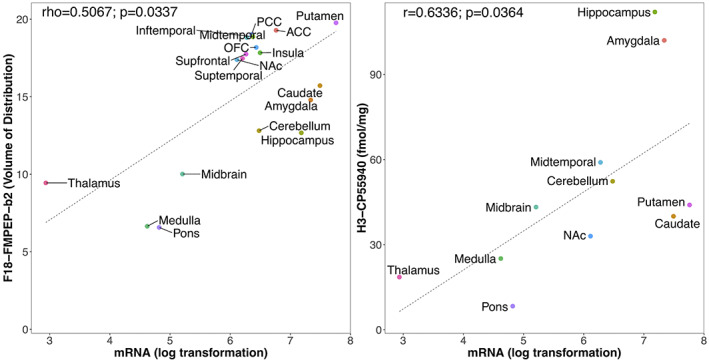

Mean distribution of F18‐FMPEP‐d2 PET scans from 36 subjects is visualized in Figure 1. The distribution of CNR1 mRNA expression and V T of F18‐FMPEP‐d2 PET from each ROI is shown in Figure 2. Strong auto‐correlation was observed both for V T from F18‐FMPEP‐d2 PET scans (inter‐subject: mean correlation coefficient rho: .8674) and for CNR1 mRNA expression from the Allen Human Brain Atlas (inter‐probe: mean correlation coefficient rho = .9148), which ensures consistency of observations. Between V T of F18‐FMPEP‐d2 PET scans and CNR1 mRNA expression from 18 ROIs, moderate strength of correlation was observed (rho = .5067, p = .0337). The correlation between V T of F18‐FMPEP‐d2 PET scans and mRNA was significant in subcortical regions (rho = .8182, p = .0068), not in cortical regions (rho = .5952, p = .1323). Strong positive correlation was also found between CNR1 mRNA expression and H3‐CP55940 binding from 11 ROIs (r = .6336, p = .0364), which validates the finding between F18‐FMPEP‐d2 PET scans and CNR1 mRNA (Figure 3). The correlation between V T of F18‐FMPEP‐d2 PET scans and H3‐CP55940 binding from 15 ROIs was not significant (r = .5025, p = .0563). The slope estimates (slope = 4.3192; p < .0001) of the regression were used to transform F18‐FMPEP‐d2 PET atlas into density map atlas (Figure 4, https://neurovault.org/images/782713/).

Our main finding was that CNR1 mRNA expression was moderate to strongly correlated with CB1 receptor availability from V T of F18‐FMPEP‐d2 PET, showing the association of CNR1 mRNA expression with CB1 receptor. The correlation between V T of F18‐FMPEP‐d2 PET scans and H3‐CP55940 binding was marginally significant, and density map atlas of CB1 receptor was produced. From the meta‐analysis, the moderate to strong correlation was observed between mRNA expression from the Allen Human Brain Atlas and protein expressions from PET/SPECT scans across multiple genes, with the pooled correlation coefficient of .76, which was stronger than the correlation coefficient of .5067 between F18‐FMPEP‐d2 PET scans and CNR1 mRNA in this study.

The association between CNR1 mRNA expression and protein expression from either PET scans or autoradiography showed the moderate to strong correlation, despite samples stemming from unrelated populations. However, we also have to consider that there are many complex and various post‐transcriptional mechanisms that are involved in turning mRNA into protein (Rizzo et al., ref. 2016). mRNA transcripts interact with intra, extracellular stimuli, and are modified, regulated by non‐coding RNAs (Di Liegro et al., ref. 2014), which have an influence on protein expression for each cell type (Cheng et al., ref. 2005; Rizzo et al., ref. 2014). In addition, technologies regarding measurement of either mRNA or protein expression may not be perfectly accurate (Veronese et al., ref. 2016). Calculation of mRNA expression for each probe has its advantages and disadvantages (Arnatkeviciute et al., ref. 2019). Therefore, probe selection has an impact on the final results of mRNA expression (Arnatkeviciute et al., ref. 2019). In this study, we selected the median gene expression within each ROI to minimize the possible bias from probes. Also, mRNA expression is analyzed in the cytoplasm, while CB1 receptor is predominantly expressed in the cell membrane, presynaptically (Mechoulam & Parker, ref. 2013). However, genomic atlas does not provide an accurate mapping at a cellular level, and mRNA expression as well as protein expressions from PET scans and autoradiography are averaged within each ROI, yielding representative expression values. Also, autoradiography provides far less spatial information than other technologies (Beliveau et al., ref. 2017) and can be acquired only from postmortem states. These differences in PET scans and autoradiography might affect non‐significant association between V T of F18‐FMPEP‐d2 PET scans and H3‐CP55940 binding.

Previously, the association of brain mRNA mappings of the Allen Human Brain Atlas with several PET‐derived protein expressions has been investigated, including serotonin receptors (Beliveau et al., ref. 2017; Komorowski et al., ref. 2017; Rizzo et al., ref. 2014), serotonin transporters (Beliveau et al., ref. 2017; Komorowski et al., ref. 2017), opioid receptors (Rizzo et al., ref. 2014), dopamine receptors (Komorowski et al., ref. 2020), and monoamine oxidase A (MAO‐A) (Komorowski et al., ref. 2017; Zanotti‐Fregonara et al., ref. 2014). The correlation coefficient ranged from −.10 between 5‐HTT mRNA and C11‐DASB PET to .99 between GRM1 mRNA and F18‐FIMX PET. We included one result with the strongest correlation between each radiopharmaceutical from single institution with one mRNA expression, as several studies report the association between a single radiopharmaceutical with several mRNAs. The presently observed correlations for CB1 (rho = .5067, p = .0337) was slightly weaker than the pooled result of this meta‐analysis. Even in the same neurotransmitter system, there was a difference in the associations between mRNA expression and protein expression according to the receptor or transporter. With the same gene expression of HTR1A mRNA from the Allen Human Brain Atlas, a wide range of correlation coefficients with protein expression has been shown; .75–.95, probably due to the characteristics of radiopharmaceuticals and ROIs included in each study. In addition, the majority of the studies included only a small number of subjects, typically <30. However, the moderate to strong correlation was observed between mRNA expression and protein expressions across multiple genes, showing the association of genes with protein levels of human brains. Recently, Hansen et al. reported the correlation between mRNA expression and multiple neurotransmitter receptors and transporters including CB1 receptor (Justine et al., ref. 2022). Poor spatial correspondences between mRNA expression and protein expression from PET scans were observed, except for 5 metabotropic receptors including CB1 receptor with a correlation coefficient of .66 (Justine et al., ref. 2022). However, their report did not include the relevant autoradiographic finding. In addition, subjects were scanned with the different radiopharmaceutical of C11‐OMAR with this study, making it difficult to compare with our result. There are a number of limitations that should be taken into account. First, F18‐FMPEP‐d2 PET scans were acquired from young males included in previous studies on feeding behavior and obesity (Kantonen, Karjalainen, et al., ref. 2021; Kantonen, Pekkarinen, et al., ref. 2021). Although no effect of age on CB1 receptor was reported in previous studies (Borgan et al., ref. 2019; Hirvonen et al., ref. 2012, ref. 2013), there is a difference in the age of participants between PET scan, autoradiography, and Allen Human Brain Atlas. The sample size of Allen Human Brain Atlas (n = 6) is too small to evaluate the age effect on mRNA expression and to give accurate result of the degree of correlation. In addition, the autoradiography study (Glass et al., ref. 1997) provides the average density of H3‐CP55940 binding in the adult human brain, without the density of each subject. Therefore, age could not be included as a covariate in this study. Second, while making the density atlas map of CB1 receptor, an area devoid of CB1 receptor would be estimated to have positive value of CB1 receptor density. A more accurate estimation for the linear conversion of V T to receptor density would be set the intercept = volume of non‐displaceable uptake. The linear conversion to receptor density will be erroneous for small V T. However, we used V T as the outcome measure to keep the results comparable with previous reports on the same CB1 receptor dataset (Kantonen, Karjalainen, et al., ref. 2021; Kantonen, Pekkarinen, et al., ref. 2021). Third, the method of calculation of mRNA expression from the Allen Human Brain Atlas and V T of F18‐FMPEP‐d2 PET might have an impact on the final results of this study. Further studies are needed to examine the association between protein expression based on multiple PET radioligands and gene expression with a uniform method.